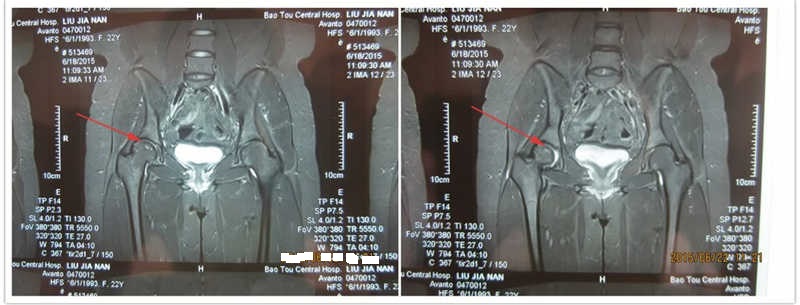

3.保守治疗时间太长,不能承受。保守治疗股骨头坏死,要想完全治好,根据病情严重程度不同,确实需要比较长的时间,有的甚至的1~2。但是这不表示,在这期间你必须住院。在经过前期的治疗后,患者完全可以在家自行用药。如内蒙古佳楠,21岁,2013年8月因为股骨头坏死来金冠医院治疗,当时佳楠的左侧股骨头有死骨,部分塌陷和骨质的破坏,使用金冠医院的靶位体液渗透疗法治疗1年,股骨头恢复健康。这期间佳楠并没有都在医院。